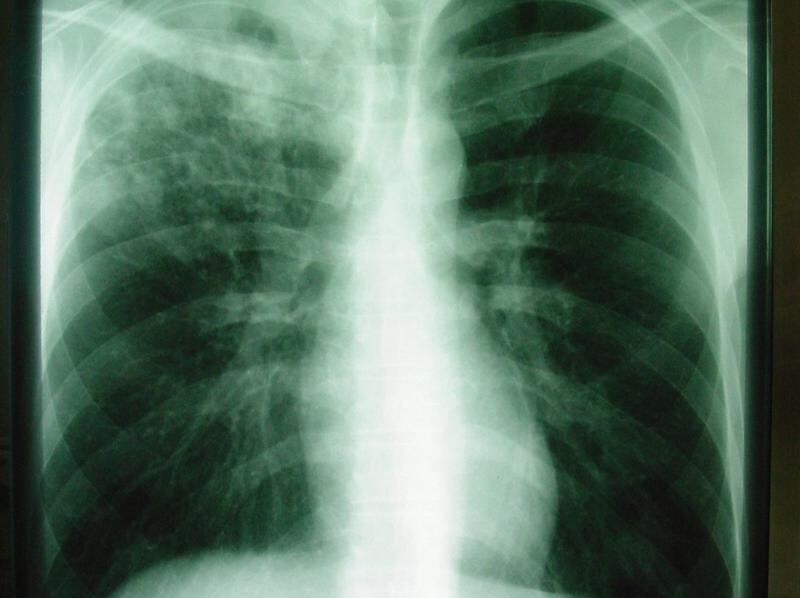

Das Röntgenbild zeigt eine offene Tuberkulose. Foto: Robert-Koch-Klinik Leipzig